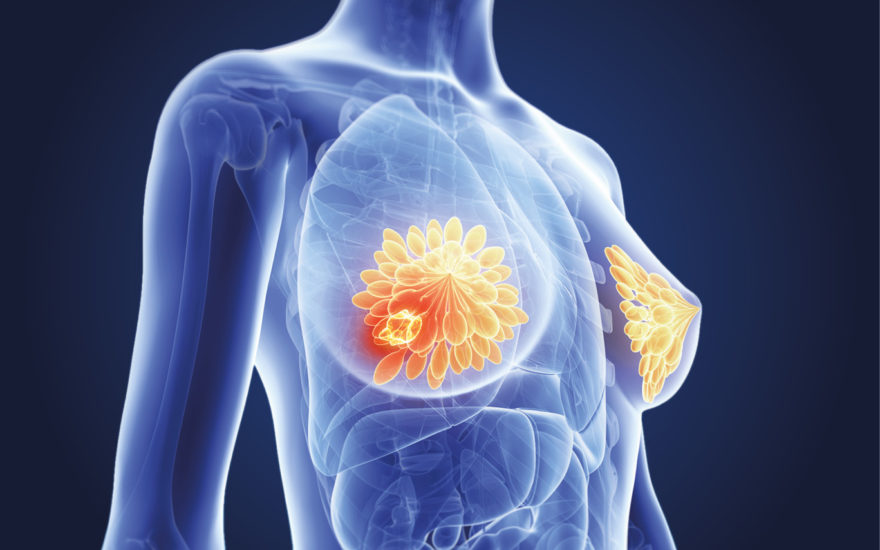

Kanceri i gjirit nuk ka një moshë specifike për të prekur gratë. Mund të prekë gratë e reja si dhe gratë e moshuara. Por a ndikon ndryshe tek gratë e reja?

Sa i përhapur është kanceri i gjirit tek gratë e reja?

Mosha e saktë e konsideruar “e re” për të pasur kancer të gjirit ndryshon. Sidoqoftë, shumica e studimeve shkencore i referohen grave më të reja me kancer të gjirit në moshën 35, 40 ose 45 vjeç.

Në hulumtimin të fundit të shfaqur në revistën “Breast Cancer Research and Treatment”, shkencëtarët shqyrtuan të dhënat që kërkonin dallime në incidencën e kancerit të gjirit tek gratë 20-49 vjeç. Në atë grup moshë, rreth 77% e diagnozave të kancerit të gjirit ndodhën tek gratë e moshës 40-49 vjeç. Studiuesit gjithashtu zbuluan se në gratë më të reja se 45 vjeç, shfaqja e kancerit të gjirit ishte më e lartë në mesin e grave me ngjyrë.

Hulumtimi i ri tregon se kanceri i gjirit tek gratë më të reja:

-mund të jetë më agresiv, invazive dhe rritet shpejt.

-diagnostikohet me vonesë.

-ka një gjasë më të lartë për të qenë negativ.

-ka një shkallë më të lartë të përsëritjes.

Përveç kësaj, disa hulumtime tregojnë se obeziteti gjithashtu mund të rrisë rrezikun e llojeve të caktuara të kancerit të gjirit tek gratë e reja. Shumica e studimeve kanë treguar që obeziteti të shoqërohet me një rrezik më të ulët të kancerit të gjirit me receptorë estrogjenikë dhe një rrezik më të lartë të kancerit të gjirit negativ në gratë para menopauzës. Shpesh, mjekët diagnostikojnë kancerin e gjirit në një fazë të mëvonshme tek gratë e reja sesa tek gratë e moshuara. Arsyet për këtë nuk janë kuptuar plotësisht. Një arsye e mundshme mund të jetë se shumë gra nuk janë në dijeni se kanceri i gjirit mund të ndodhë në moshë të re, gjë që mund të vonojë diagnozën dhe trajtimin. Gjithashtu, indet e gjirit tek gratë e reja mund të jenë më të dendura, duke e bërë të vështirë gjetjen e tumoreve gjatë vetë kontrolleve të gjirit dhe mamografisë.